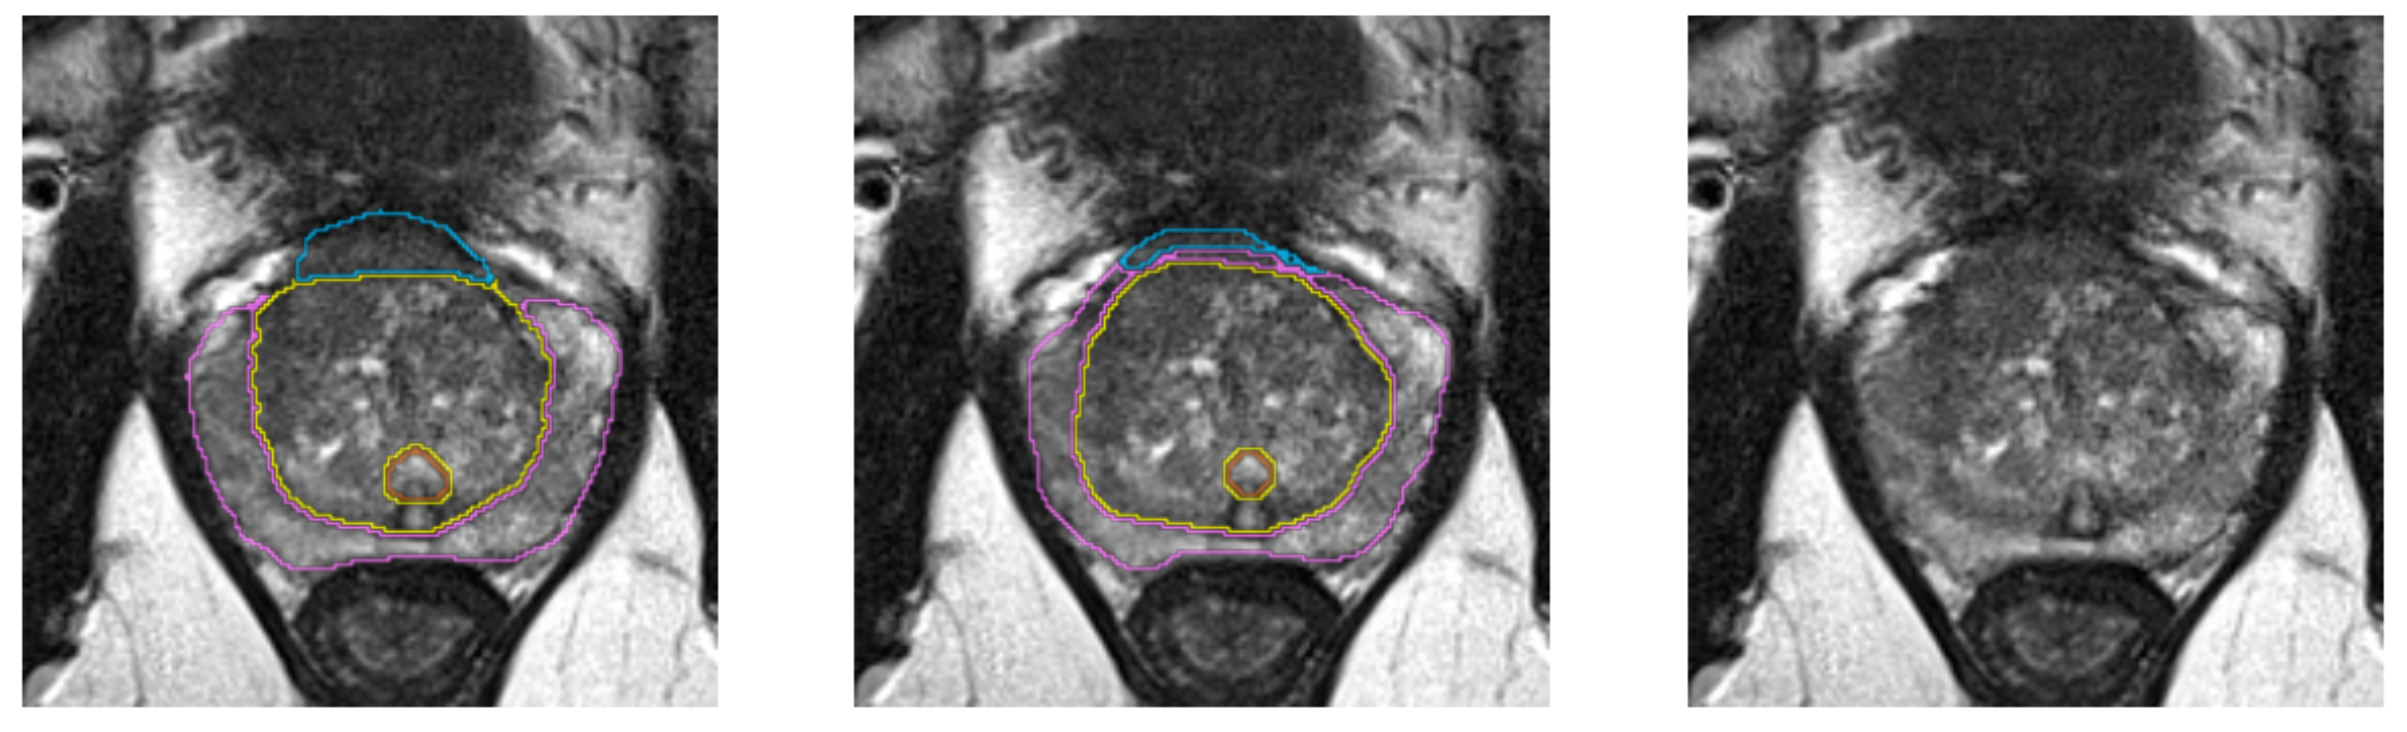

Segmentation Example 2